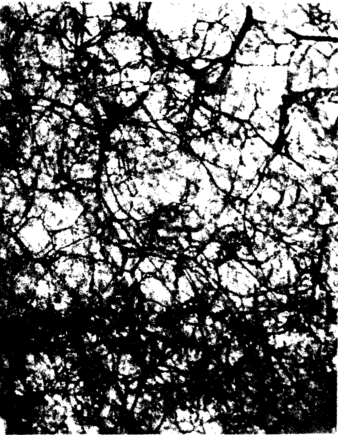

三、肩胸区皮瓣血管构筑

3例尸体肩胸区取材的皮肤分层透明标本观察所见:皮肤动脉在穿过浅筋膜时分支较少,一旦到达真皮下层则立即分成数条分支呈水平方向展开,并与相邻动脉分支吻合成网,形成真皮下血管网(图一),该血管网没有静脉伴行。来自乳头下静脉网的静脉支及浅筋膜层的静脉,在真皮下动脉网深面汇合成非伴行性浅静脉网或较粗大的浅静脉干(图二)。乳头下微静脉的管径大(30~60um)而密集。浅筋膜内与微动脉伴行的静脉管径细小(10~20um)稀疏,在脂肪间隔处吻合较少,但其汇入的浅筋膜层非伴行静脉则管径很粗大。

图一 、人体胸肩峰皮瓣的真皮下血管网 |